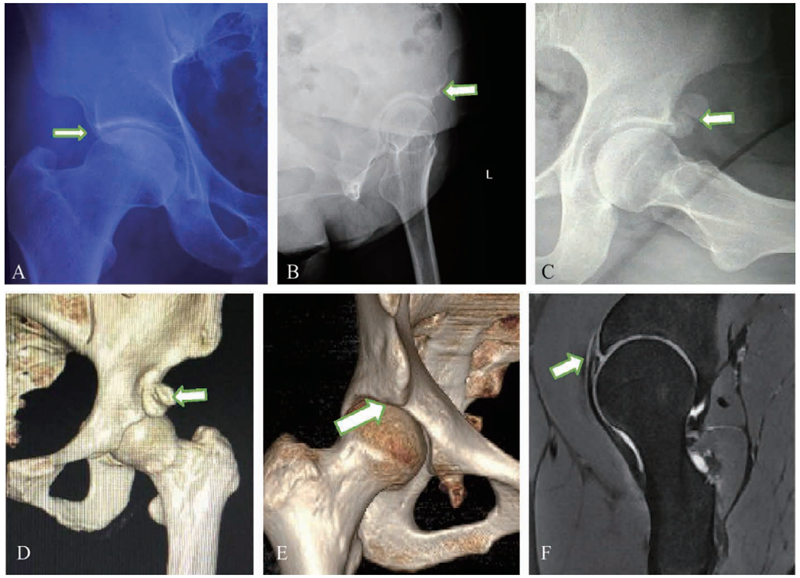

对于可疑的SSI患者,需要进行系统的影像学评估,包括骨盆X线正位及65°假斜位摄片、三维CT和MRI检查。AIIS的突出状况、有无撕脱性骨折、股直肌腱的钙化以及股骨颈的囊性变都应当在影像学评估中被重视。目前认为,三维CT是评估AIIS形态的最佳方式,MRI/MRA可以对盂唇和软骨的损伤进行细致的评估(图2)。

图2 AIIS形态的影像学表现

A.骨盆前后位X线片显示AIIS和髋臼前缘形成部分重叠,可能被忽视或被判读为交叉征阳性;B.65°假斜位X线片,可以显示AIIS的大致形态;C.Dunn位X线片显示AIIS异常骨突和头颈部的撞击关系;D.CT三维重建显示AIIS的形态;E.CT三维重建显示Ⅱ型AIIS和头颈部Cam畸形同时存在,使得屈髋位棘下间隙更加狭窄,盂唇受到对冲挤压;F. MRI显示盂唇撕裂